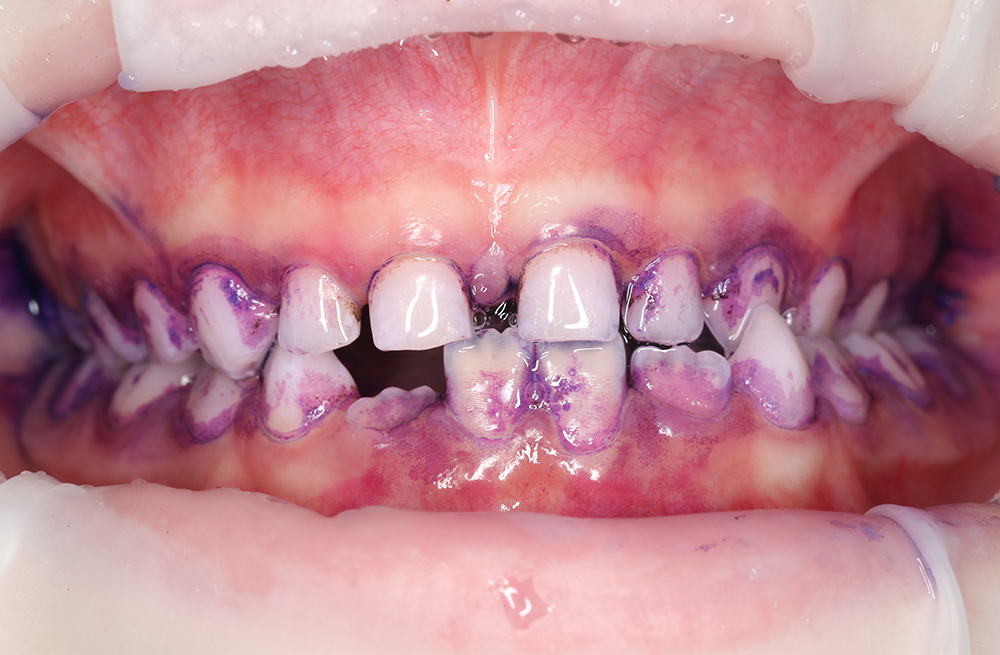

Удаление мягкого и пигментированного налёта у подростка с использованием Air-flow